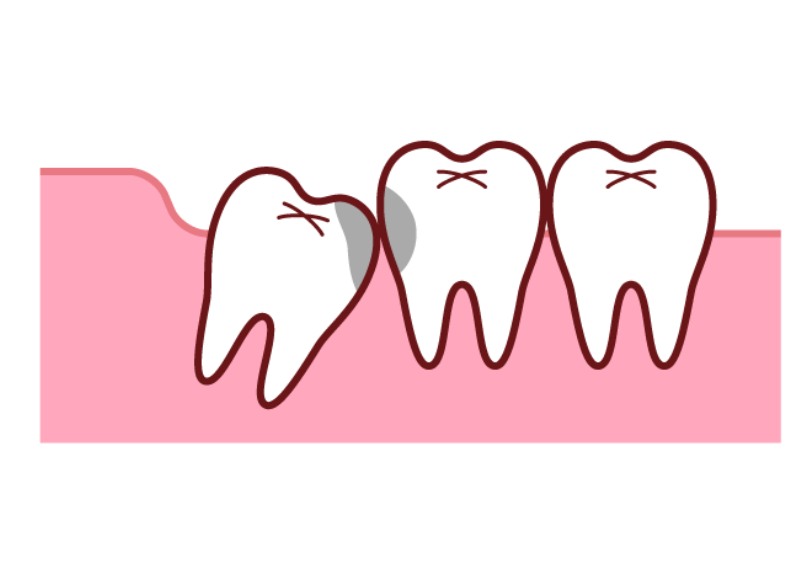

そのため横向きや斜めに傾いて生えたり、骨の中に完全に埋まったままだったりと正常な位置に生えてこられないケースが非常に多く見られます。

一番奥にしかも傾いて生えている親知らずは、歯ブラシが届きにくく非常に磨き残しが多い場所です。

親知らず自体が虫歯になるのはもちろんのこと、さらに問題なのはその手前にある大切な「第二大臼歯」まで虫歯や歯周病にしてしまうリスクが非常に高いことです。

横向きに生えた親知らずが手前の歯を前へ前へと押し続けることで、全体の歯並びが少しずつ乱れてくることがあります。

特に一度矯正治療で整えた歯並びが、後戻りする原因となることも少なくありません。